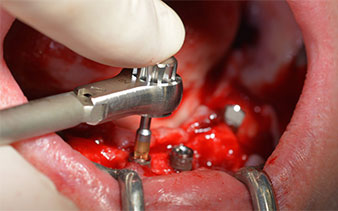

The surgical protocol for the implants employed (SKY, bredent medical) specifies a speed of 1,200 rpm for the pilot drilling (Fig. 7 - 9).

Fig. 7

speed of 1,200 rpm

Fig. 8

Fig. 9

This corresponds to the next preset position in the Implantmed. Here we see the W&H contra-angle handpiece being held at a 45° angle to mesiocaudal in the region of 45 in order to preserve the mental nerve. The mental foramen is used as the anatomic reference for all drilling in this region. The subsequent holes were drilled at a reduced speed of 300 rpm (Fig. 10 and 11).

W&H contra-angle

Fig. 10

speed of 300 rpm

Fig. 11